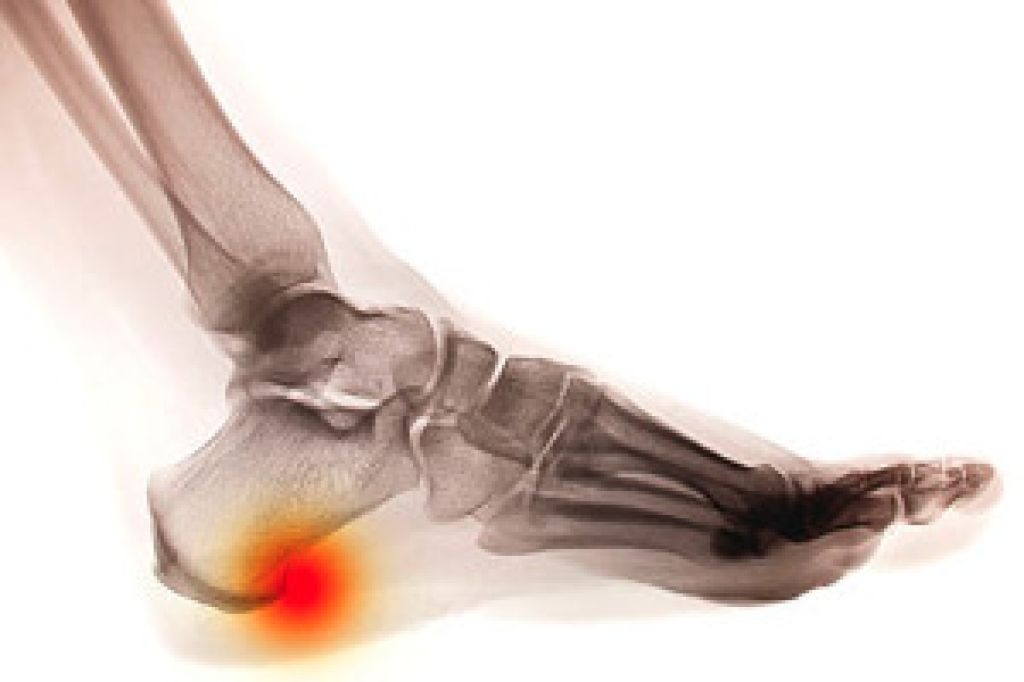

Although most people try to avoid foot trauma such as banging, stubbing, or dropping heavy objects on their feet, the unfortunate fact is that it is a common occurrence. Given the fact that toes are positioned in front of the feet, they typically sustain the brunt of such trauma. When trauma occurs to a toe, the result can be a painful break (fracture).

Severe toe fractures may be treated with a splint, cast, and in some cases, minor surgery. Due to its position and the pressure it endures with daily activity, future complications can occur if the big toe is not properly treated.